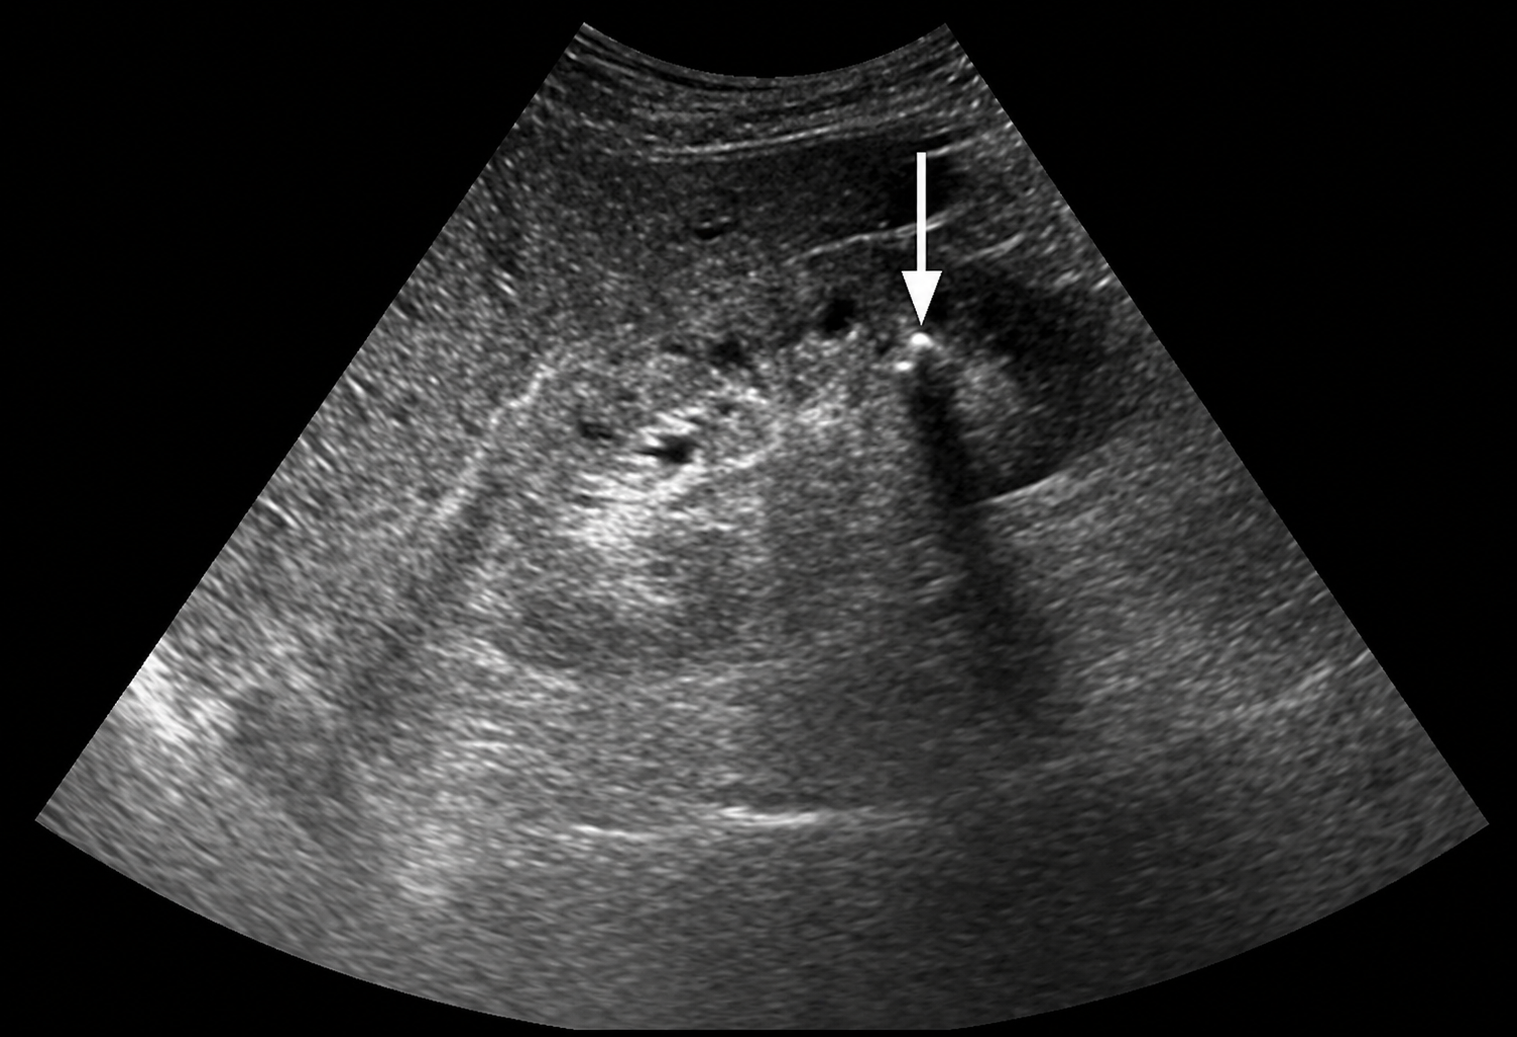

Kết quả xét nghiệm hình ảnh khiến tất cả phải bàng hoàng khi xác nhận sự hiện diện của rất nhiều sỏi trong thận.